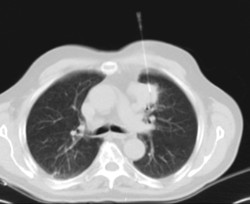

CT-guided thoracic FNA (fine needle aspiration)

PAAF (Punción) Tórax guiada por TCProva que consisteix en obtenir una mostra de teixit de lesions toràciques, com per exemple masses pulmonars, mediastíniques, lesions òssies, etc. Per a tal s'administra anestèsia local sobre la zona de punció, que es realitza amb agulles de calibre fi. Tot el procediment es realitza controlat per imatges obtingudes per Tomografia Computaritzada (TC) en diversos moments de la punció mitjançant l'ús de Fluoroscòpia- TC. Després de la prova, el pacient resta unes hores hospitalitzat. És necessari que porti les proves de coagulació abans de la punció.